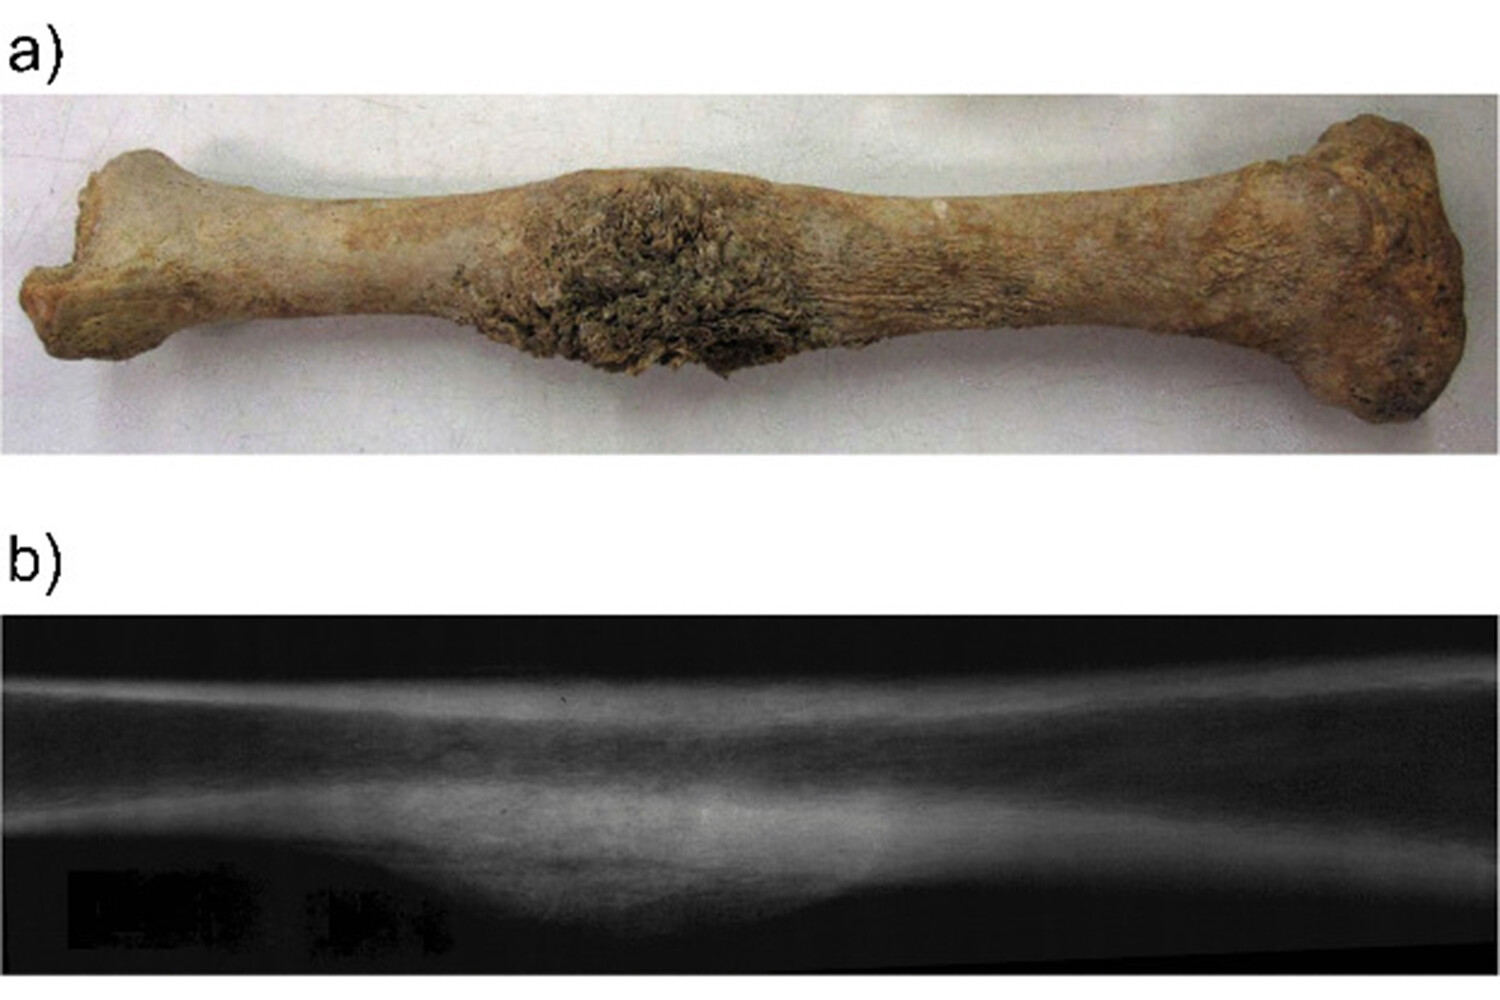

Палеопатологическое исследование показало, что у индивида была остеосаркома (злокачественная опухоль кости), вызвавшая обширные дегенеративные изменения на правой большеберцовой и малоберцовой костях, а также лепра.